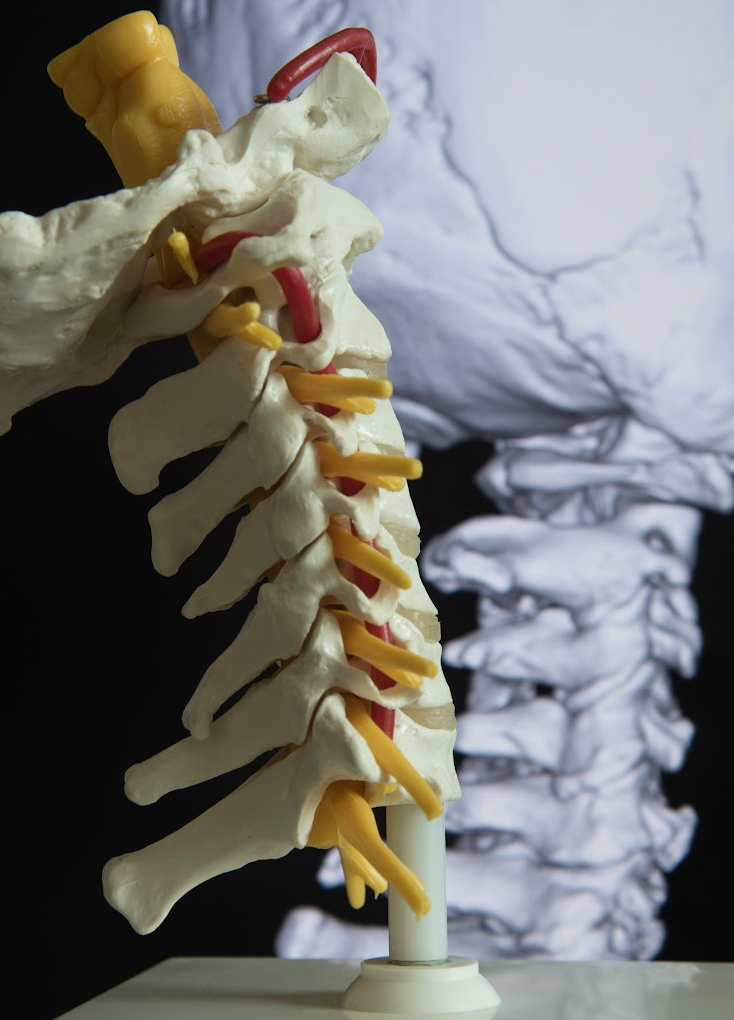

Every single one of these functions – and all the rest that happen without you having to help the process along, like digestion, or vision – are all thanks to your nervous system. This complex network of cells and nerves carries messages from the brain out to every part of the body, all the way down to your toes.

If you think it, say it, or feel it, the nervous system is involved. As you can guess, the nervous system affects every aspect of your health. That includes your movement, thoughts, senses, sleep, stress response, and all bodily processes. Your nerves receive information from the world around you. Then, the nerves interpret that information and control your response.

Think of the nervous system like a giant information highway that runs across your entire body.

Anyone with concerns about nerve problems or the health of their nervous system may do well to consult with a Chiropractor. Why?

Chiropractors are experts in the spine, muscles, and the nervous system! If a neuromusculoskeletal condition is present, we can provide an effective treatment that may manage the symptoms you have. We are qualified to treat the joints, muscles, bones, and soft tissues that keep you going every day. The benefits you may be able to look forward to include the alleviation of pain, the promotion of health, and a fantastic improvement to your quality of life!